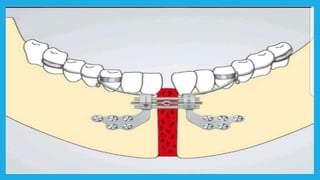

Surgical assisted rapidpalatal expantion(SARPE)